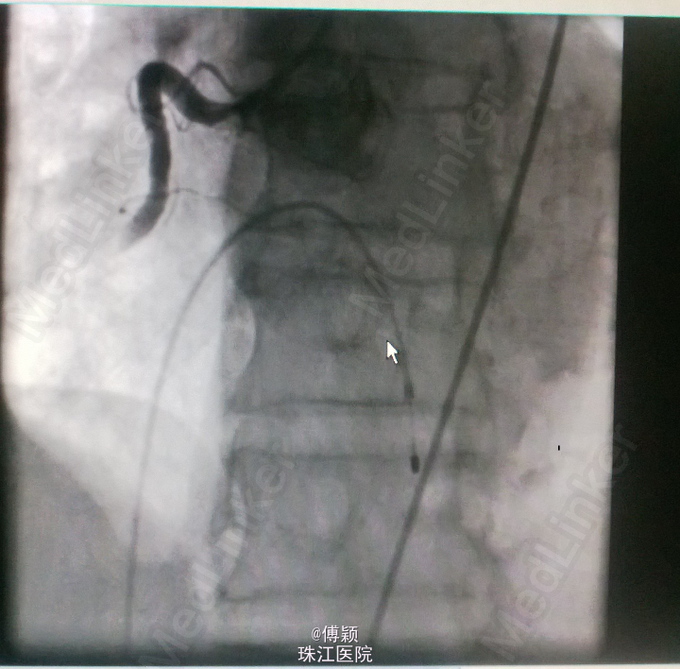

诊断:1.急性下壁心肌梗死(STEMI),心源性休克,心功能IV级(killip分级);2.高血压病2级(很高危);3.2型糖尿病;4.陈旧性脑梗塞;5.高尿酸血症。 处理——收入CCU后立即转去导管室行急诊冠脉造影术,术中见右冠中段以远全部闭塞,未见侧枝循环,前降支近中段见节段性狭窄70-80%,术中经6F Thrombuster血栓抽吸导管反复多次抽吸右冠,抽出数条红色血栓,并于右冠中段病变处植入Firebird 4.0*23mm药物支架,缝合鞘管时患者心电监护提示加速性实行逸博心律(110次/分左右),5min后突发室速、室颤,立即予床边电极除颤后转位室性逸博心律(105次/分)。返回病房后夜间患者多次出现室颤,予点击除颤、胺碘酮静滴等治疗后好转。术后24h内患者出现少尿,予静脉补液(5000ml/天左右)、利尿等,患者尿量基本维持在2000ml/天。术后辅查心电图见下壁导联ST段明显回落。余予抗血小板聚集、稳定斑块等治疗。